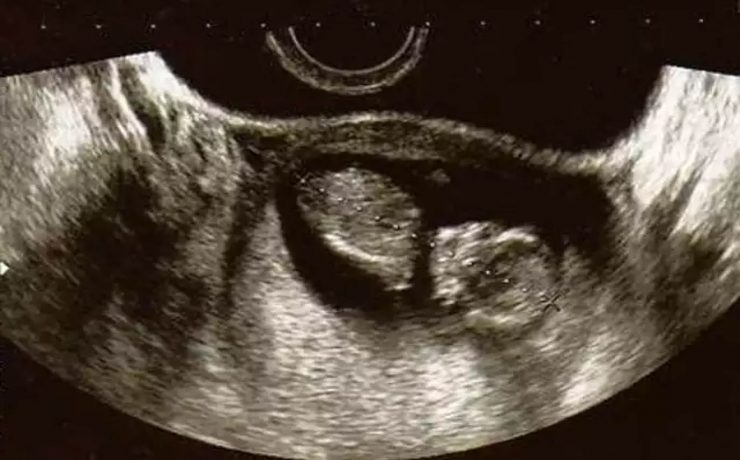

Introducción: El cáncer de endometrio es la segunda neoplasia ginecológica a nivel mundial ,más común en la perimenopausia , la incidencia es de 6 veces mayor en países desarrollados que en los menos desarrollados. La supervivencia en etapas tempranas es del 80%. Estudios de tamizaje Escrutinio a partir de los